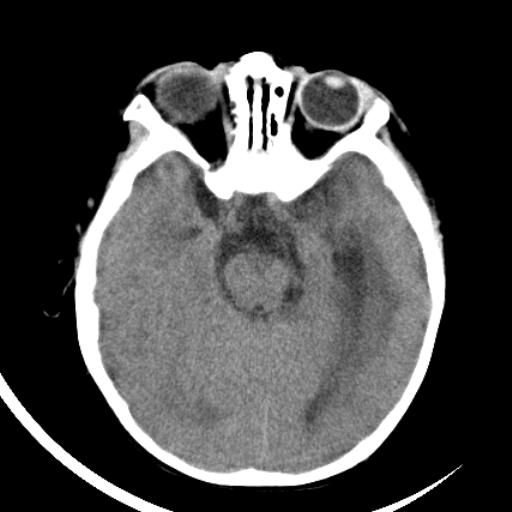

双侧脑室前后角周围白质片状低密度影,双侧侧脑室旁、双顶叶皮层及皮层下多个小原点状钙化灶,不除外torch感染。右顶叶脑回似乎较对侧大,建议mri检查以除外脑发育异常。

考虑:1、巨脑回畸形(皮质明显增厚+脑回明显增宽+白质减少)。

2、torch综合征(室管膜下钙化+白质内及皮髓质交界处多发钙化)。